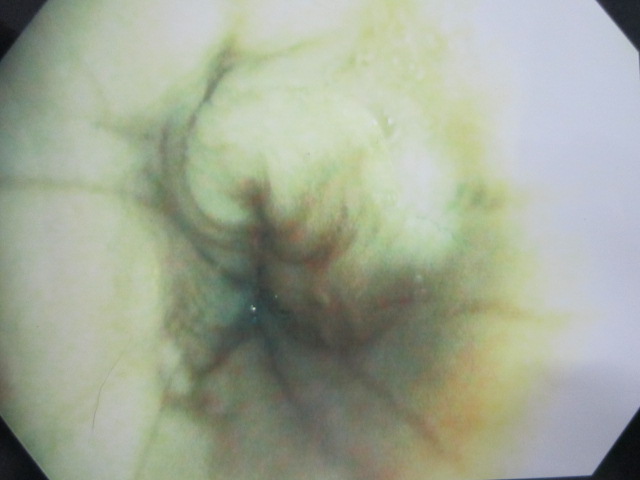

術前

術前のレントゲンです。

食道に異物がつまっています。

IMG_5039

食道に砂ぎもがつまっています。